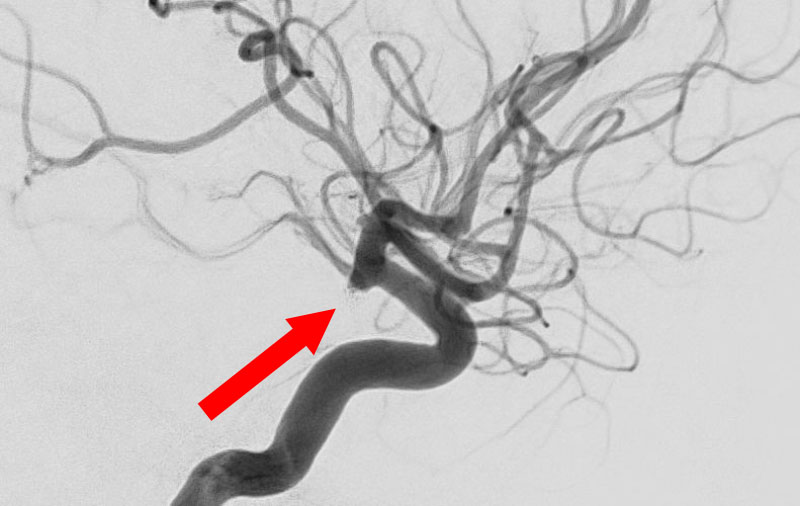

No.1591 手術前

No.1591 手術中

No.1591 手術後